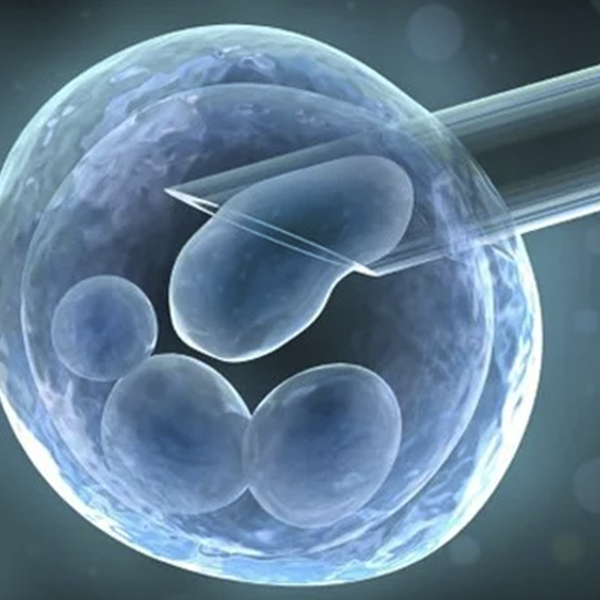

Egg retrieval from the donor:The growth and development of the eggs produced will be monitored closely using blood tests and ultrasounds. Once the ovarian follicles reach an appropriate size, a trigger medicine is given for the final maturation of the eggs and ovulation. A minor surgical procedure is performed under sedation to retrieve the eggs from the ovaries using an ultrasound-guided needle.

Embryo transfer to the recipient:For this step, either the fresh embryos can be used directly or frozen embryos previously created from the donors can be used after thawing them. The embryos will be loaded into a catheter and transferred into the recipient woman’s uterus using ultrasound guidance.